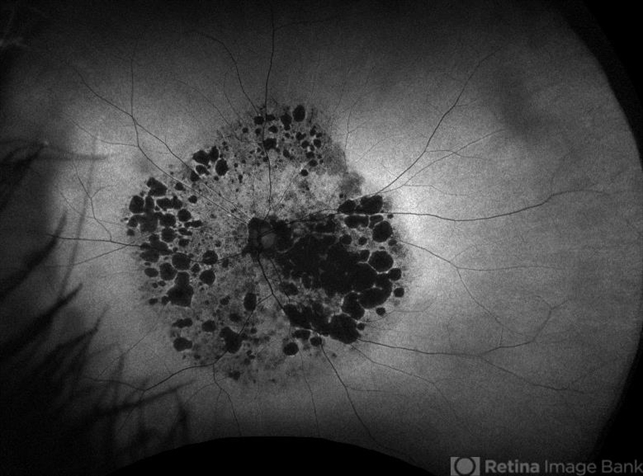

- mucopolysaccharidoses, retinitis pigmentosa (RP) dystrophy

- Cori Sturtevant, Connecticut Retina Consultants, Hamden, Connecticut

- Fundus camera

- Fundus photograph and autofluorescence of a 49 year old male with mucopolysaccharidosis type III (Sanfilippo syndrome)